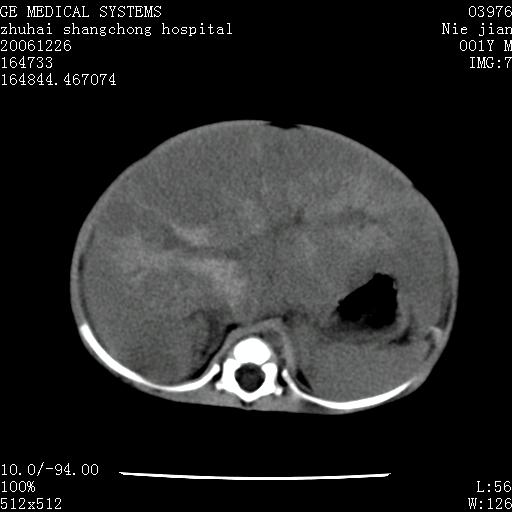

3个月婴儿腹胀来看。

【影像特征】

1、肝明显增大,肝弥漫性低密度灶。

2、肾上腺区见类圆形肿块,其内密度不均,见片状偏高密度。

【诊断】

1、肝弥漫性病变,考虑急性肝炎致广泛脂肪浸润可能性大。

2、肾上腺区占位,假性肿瘤?肾上腺血肿(感染所致)?

1、肝硬化,脂肪浸润消失。

2、假性肿瘤消失或血肿吸收。

1、关键着眼点:肝脏弥漫性病变内有没有走形的血管,仔细看部分低密度内有血管影(要有增强扫描作为证据就好了),说明并非肿瘤样病变,而是脂肪浸润。即可能不是转移瘤或原发肿瘤,低密度的形态上看,是片状,也不像肿瘤。

3、肝炎的结局是肝硬化,而恰恰一年后复查,已有肝硬化表现。肿瘤一般那会消失,那叫奇迹。

4、肾上腺出血也可见于败血症及感染,通常包块在数周内消失,ct表现包块内有偏高密度,可能是亚急性血肿的表现。假性肿瘤即腹部肠管积液、扩张血管及邻近结构的伪像。自然会消失。

5、因此,感染可以贯穿一切,解释一切。肿瘤自然消退?可能吗?那些应要无道理的创造奇迹的事情会那么容易发生吗?

楼主反馈的结果:该患儿曾在大医院看了,也劝其放弃治疗,不得已抱回家等,据说这一年中曾得过一次肺炎,做过治疗,再没别的治疗。反正一年多了还活得好好的。